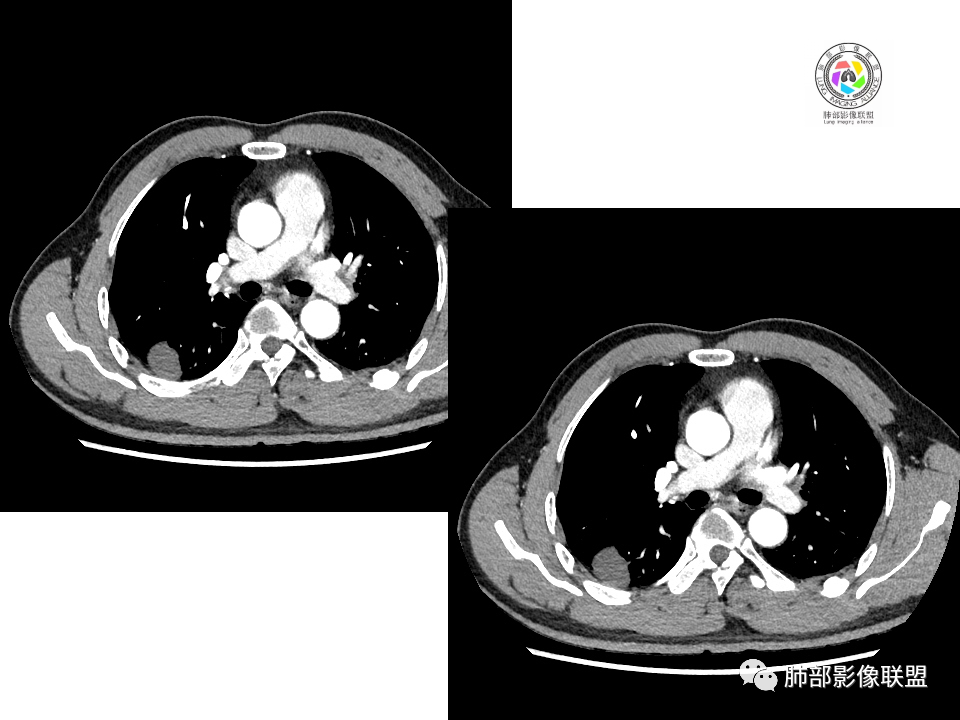

右肺下叶背段胸膜下见团块影,边缘清,其后基底段见一扁平状结节,各见‘’平直及桃尖"征,均轻度强化,右肺上叶背段及中叶外侧段分别少许纤维化灶及部分卫星病灶,一元考虑TB,与隐球菌鉴别!

右肺下叶胸膜下类圆形团块,边缘光滑无毛刺分叶,强化均匀无坏死,另血管旁小结节平直桃尖,上叶小斑片影,考虑结核或者真菌感染。

右肺下叶背段胸膜下见一边缘稍模糊、浅分叶结节灶,密度均匀,似乎轻度均匀强化(具体CT值看不出来),与胸膜锐角相贴,似有平直征和桃尖征。此病灶前内侧还有类似小结节,轻度强化,右肺上叶后段有斑片状稍高密度影:考虑良性病变,炎性结节可能。

晨读,右肺下叶背段胸膜下见肿块影,边缘清晰,未见与气管相连通,右下叶见结节影边缘清晰,两处病变密度均匀,同步不明显强化,中叶外侧段斑点状影,树芽征,考虑1良性病变,结核?隐球菌?2淋巴瘤待除外。

右肺下叶背段胸膜下宽基底团块状占位,浅分叶,边界清晰,胸膜下脂肪间隙清晰,背段支气管管壁似乎增厚,未见明显强化。外侧基底段血管束间结节,边界清晰,亦未见明显强化。中叶外侧段见少许树芽征象。纵隔未见明显肿大淋巴结。我先猜个结核。

男性,49岁,体检发现,右肺下叶背段胸膜下见肿块,边界清楚,边缘光滑,胸膜下脂肪间隙存在,有分叶,无毛刺,均匀强化,内无坏死,右肺下叶血管束间不规则实性结节,边界清楚,无明显强化,中叶少许斑片状高密度影,纵隔未见明显增大淋巴结,考虑良性病变。

2.右肺下叶背段胸膜下块影,边界清楚光整,上下极见磨玻璃晕,未见明显分叶毛刺和棘状突起,未见胸膜凹陷或胸壁侵入。密度均匀,轻度不均匀强化。未见支气管进入。

3.右肺中叶外侧段胸膜下散在小片影,磨玻璃密度为主,边界不清,支气管相关。符合炎性特征!

4.右肺下叶基底段支气管血管束旁小结节影,边界清楚,强化不明显。注意,这结节在“遥远的”基底段。